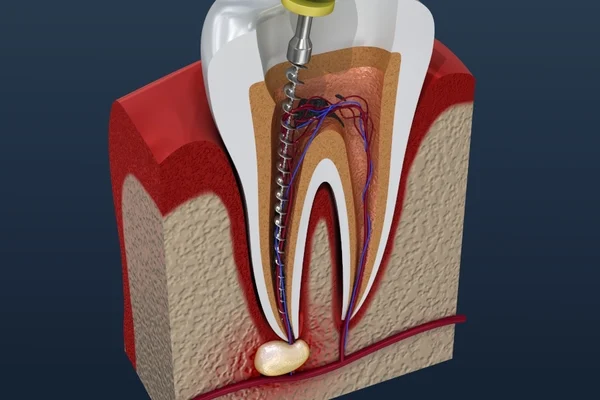

Comfortable, precision root canal therapy to save severely decayed or infected teeth — eliminating pain and preserving your natural smile.

Learn More